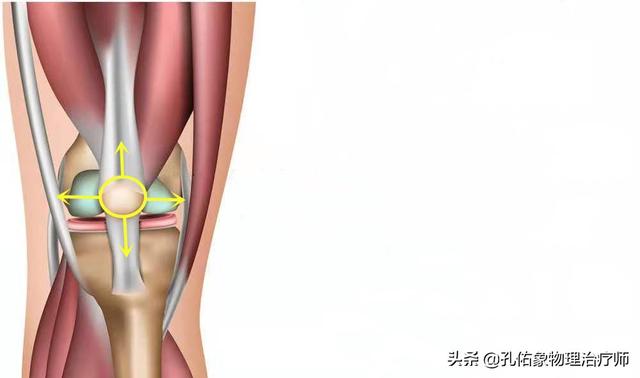

Lorsque l'on étire le genou, on constate que la rotule se déplace avec la flexion et l'extension de l'articulation du genou, et que le son émis lors de la flexion et de l'extension de l'articulation est en fait lié au mouvement de la rotule. Sous la rotule se trouve ce que l'on appelle le corps adipeux infrapatellaire, qui est un élément important de la structure de l'extension de l'articulation du genou ; le corps adipeux infrapatellaire a un effet amortisseur dans le mouvement et permet de conserver une structure harmonieuse pour le mouvement d'extension de l'articulation du genou.

D'une manière générale, ce type de structure peut entraîner une certaine usure lors de l'utilisation répétée de l'articulation du genou, ce qui a un impact sur son mouvement, et un bruit de cliquetis lors du mouvement peut en être l'une des manifestations.

Dans les articulations du genou, la surface articulaire est recouverte d'un cartilage fin et lisse afin de permettre un mouvement suffisamment souple, et en cas d'usure due à une blessure ou à une surutilisation, la surface articulaire devient inégale, et l'os glisse sur la surface inégale pendant le mouvement de l'articulation, ce qui entraîne un bruit de cliquetis. Lorsque l'articulation bouge, l'os glisse sur la surface inégale de l'articulation et un bruit de cliquetis se produit, qui peut s'accompagner d'une douleur intense.